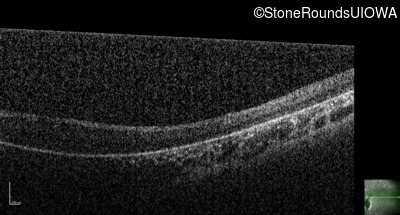

Optical Coherence Tomography - Right - Light Perception

Exemplar / OCT Stack